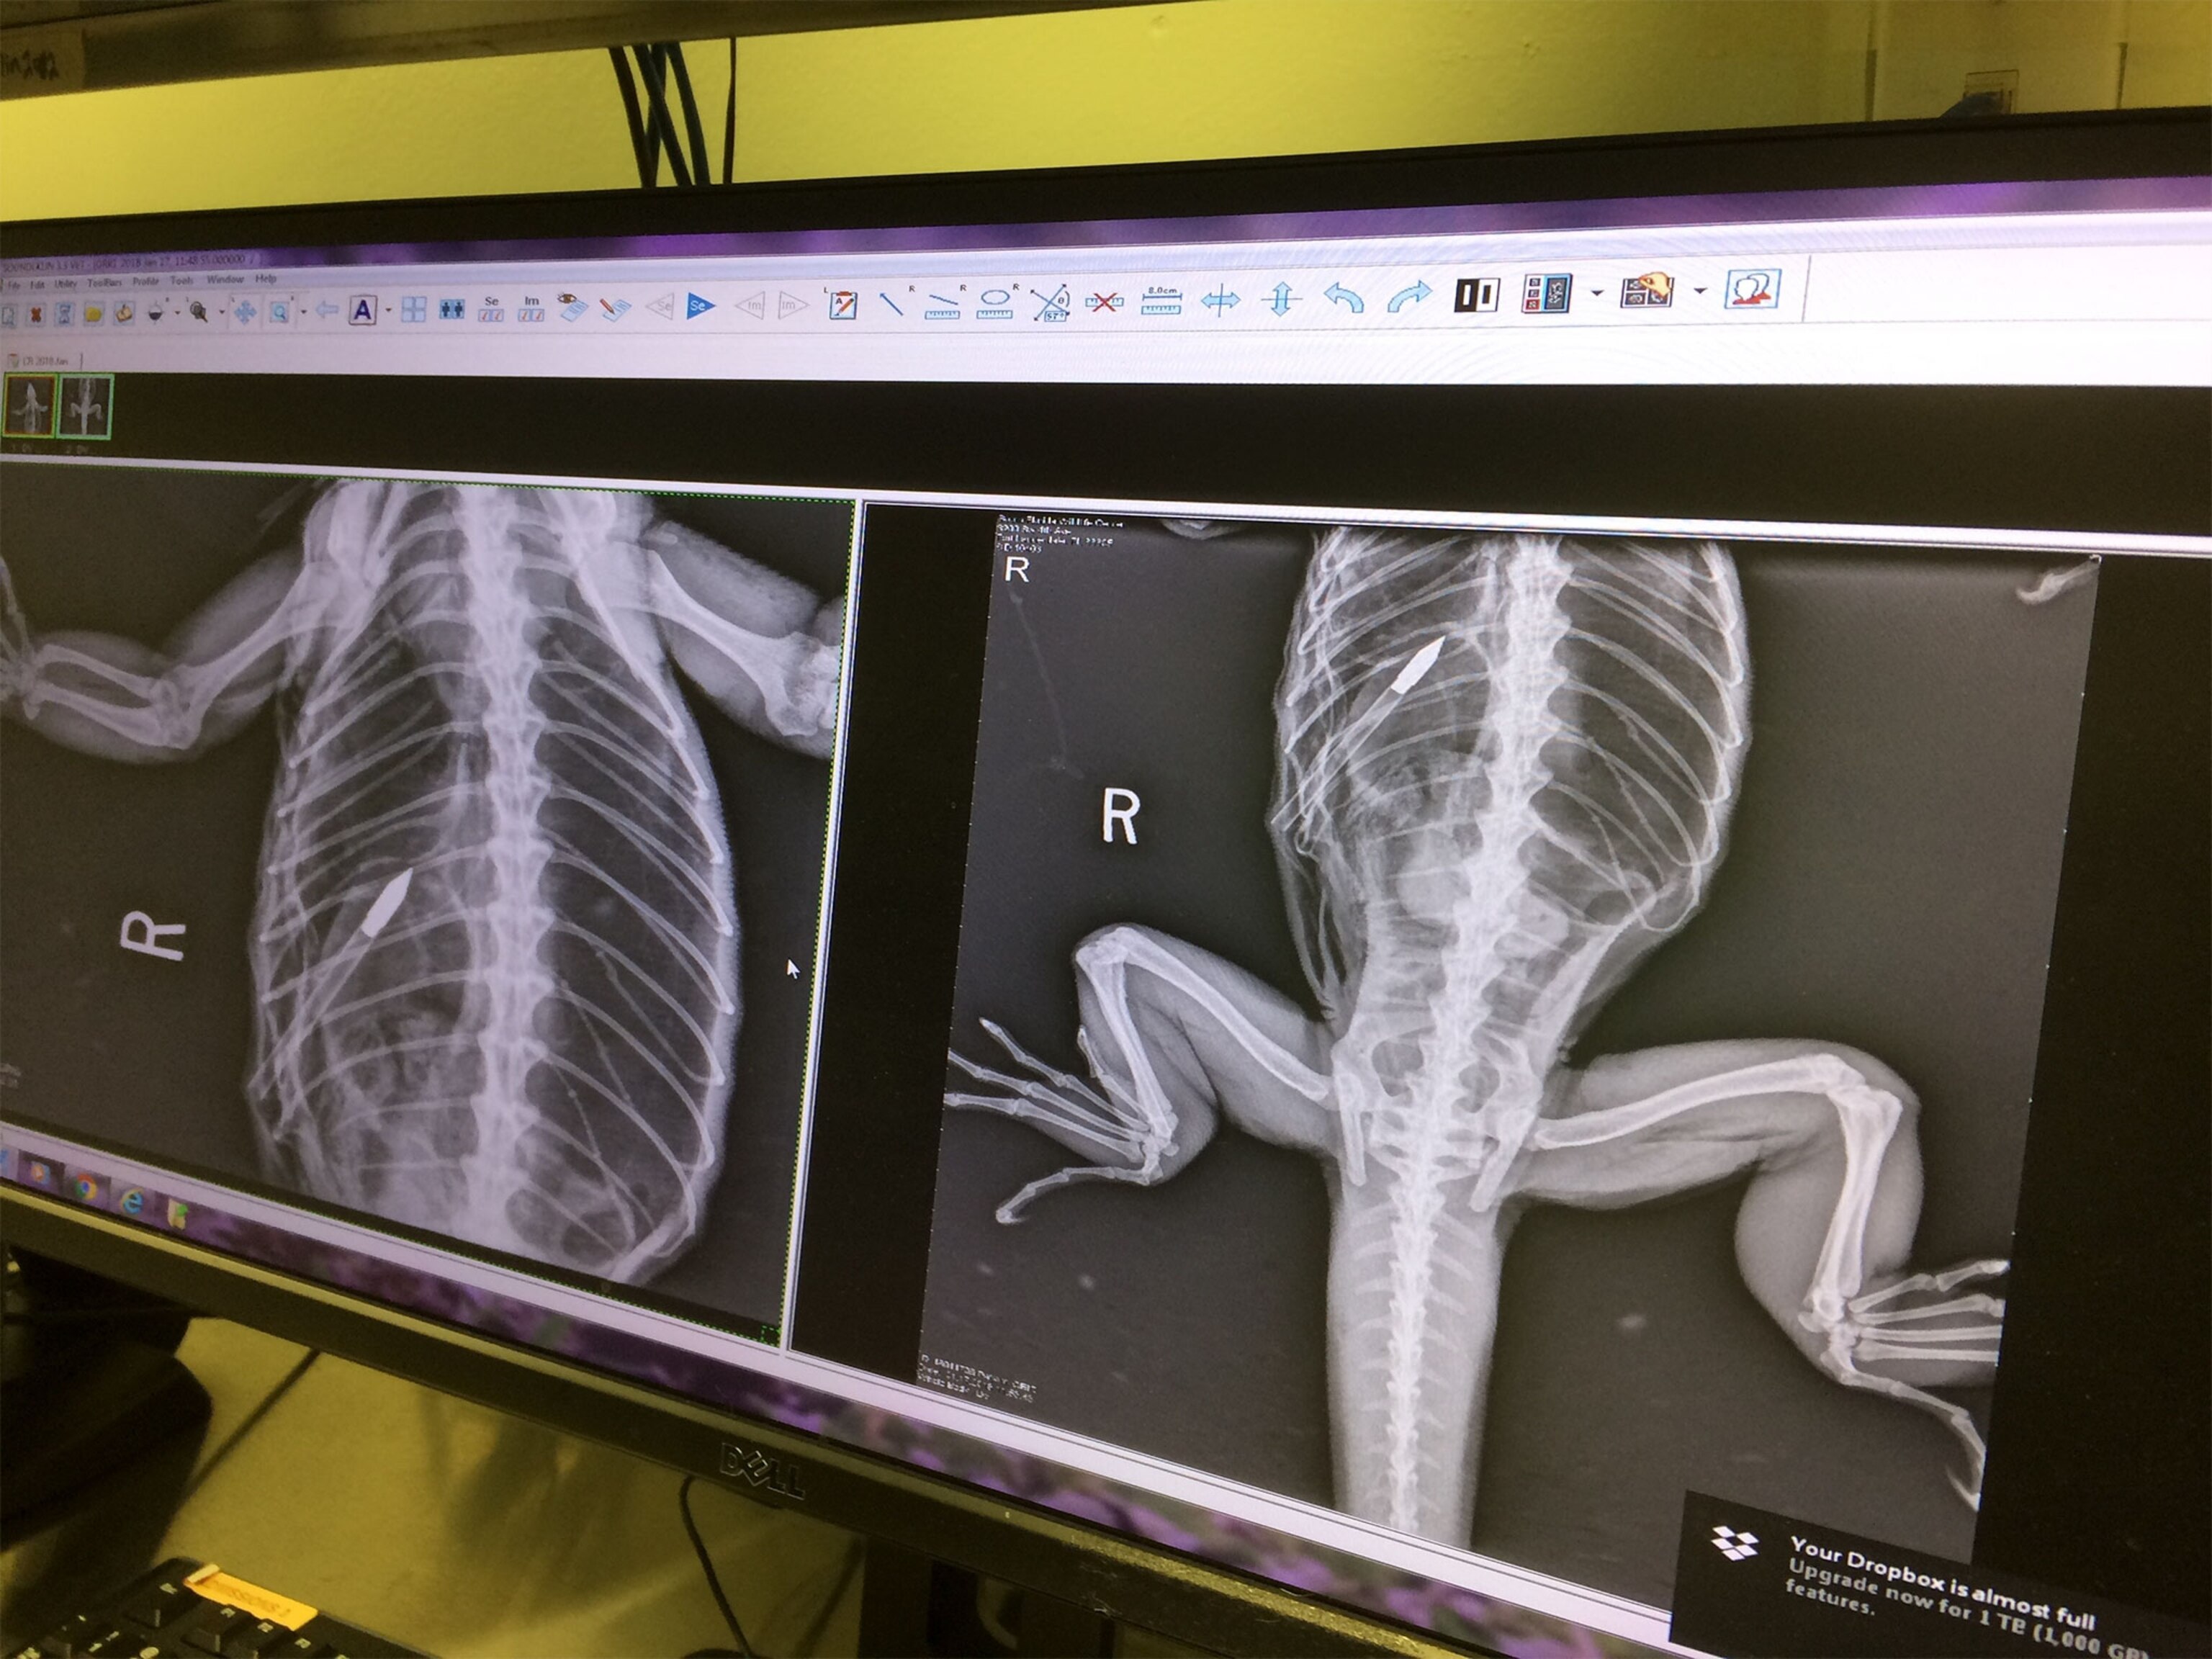

The iguana, an adult male they nicknamed “Godzilla” who is six feet long and weighs 10 pounds, was shot five times with arrows, one of which was embedded in its abdomen, and had multiple puncture wounds as a result.

When the iguana reached the wildlife center, veterinarians sedated the animal and performed surgery to remove the remaining arrows. He is now recovering, but Parsons-Drake said the prognosis is guarded: the extensive damage means a risk of internal bleeding and infection.